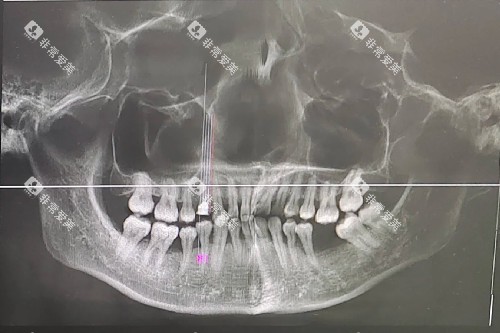

口腔状况:若存在口腔炎症、龋病等问题,修复前需先治疗,会增加总体费用。骨量不足者需植骨,额外增加2000-3000元成本。

口腔条件:邻牙健康可考虑固定桥;牙槽骨条件好可选择种植牙;多颗缺失或牙槽嵴重的吸收者可能只能选择活动义齿。